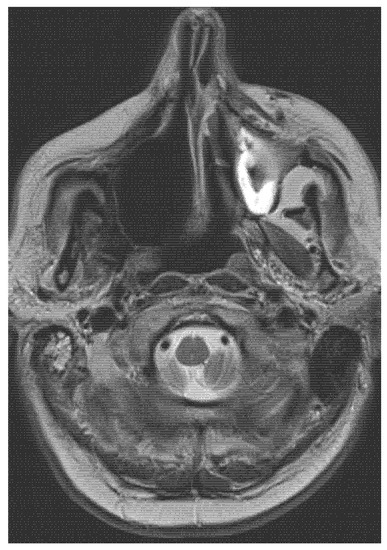

- CT, MRI scan (size, spread, and metastases of tumour mass), if necessary, PET scan, and USG.